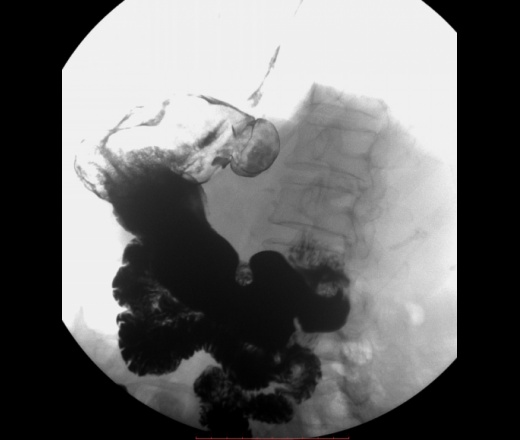

Локализация харатерная для дивертикула желудка(задняя стенка свода), тип дивертикула нехарактерный по механизму формирования, тут по типу пульсионного, характерен тракционный механизм, за счёт явлений перипроцесса. Может быть я и неправ.

"Дивертикулы желудка Дивертикулы желудка (ДЖ) встречаются очень редко, случайно они обнаруживаются в 0,02% случаев аутопсий [57]. ДЖ имеют грушевидную, реже – овальную форму, размеры их обычно небольшие, слизистая оболочка чаще не изменена. Юкстакардиальные ДЖ составляют до 75% всех ДЖ. Они наиболее часто локализуются в области пищеводно-желудочного соединения, обычно на малой кривизне желудка, чаще на задней стенке, что объясняют особенностью расположения мышечных пучков собственного мышечного слоя стенки желудка. ДЖ наиболее часто встречаются в среднем возрасте и имеют размеры от 1 до 3 см в диаметре [58, 59]. Интрамуральные или частичные ДЖ формируются путем выпячивания слизистой оболочки через мышечный слой. Такие ДЖ чаще встречаются в препилорической зоне, обычно в области большой кривизны желудка [60]. При проведении эндоскопии или бариевого контрастирования стриктуры пептические язвы и другие деформации могут иметь сходство с препилорическими ДЖ."http://helpiks.org/3-80531.html

Дивертикулы желудка (ДЖ) встречаются очень редко, случайно они обнаруживаются в 0,02% случаев аутопсий [57]. ДЖ имеют грушевидную, реже – овальную форму, размеры их обычно небольшие, слизистая оболочка чаще не изменена.

Юкстакардиальные ДЖ составляют до 75% всех ДЖ. Они наиболее часто локализуются в области пищеводно-желудочного соединения, обычно на малой кривизне желудка, чаще на задней стенке, что объясняют особенностью расположения мышечных пучков собственного мышечного слоя стенки желудка. ДЖ наиболее часто встречаются в среднем возрасте и имеют размеры от 1 до 3 см в диаметре [58, 59]. Интрамуральные или частичные ДЖ формируются путем выпячивания слизистой оболочки через мышечный слой. Такие ДЖ чаще встречаются в препилорической зоне, обычно в области большой кривизны желудка [60]. При проведении эндоскопии или бариевого контрастирования стриктуры пептические язвы и другие деформации могут иметь сходство с препилорическими ДЖ."http://helpiks.org/3-80531.html